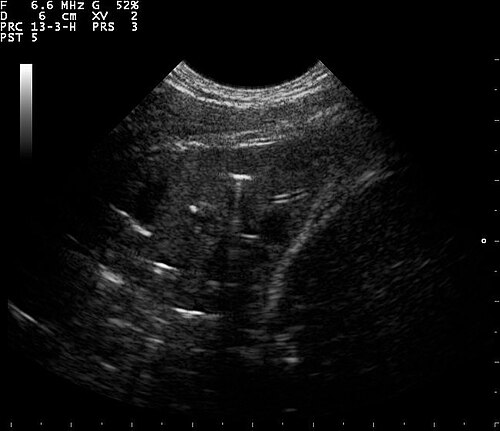

Lung Ultrasound — B-Lines (Pulmonary Fibrosis)

B-lines visible on lung ultrasound indicating interstitial disease in a patient with pulmonary fibrosis

ULTRASOUND Downloaded 2026-03-15

Ultrasound

B Mode

Wikimedia Commons: B lines on a lung ultrasound of a patient with fibrosis.jpg